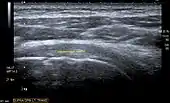

Ultrasound

There are several advantages of ultrasound. It is relatively cheap, does not emit any radiation, is accessible, is capable of visualizing tissue function in real time, and allows the performance of provocative maneuvers in order to replicate the patient’s pain.[26] Those benefits have helped ultrasound become a common initial choice for assessing tendons and soft tissues. Limitations include, for example, the high degree of operator dependence and the inability to define pathologies in bones. One also has to have an extensive anatomical knowledge of the examined region and keep an open mind to normal variations and artifacts created during the scan.[27]

Although musculoskeletal ultrasound training, like medical training in general, is a lifelong process, Kissin et al. suggests that rheumatologists who taught themselves how to manipulate ultrasound can use it just as well as international musculo-skeletal ultrasound experts to diagnose common rheumatic conditions.[28]

After the introduction of high-frequency transducers in the mid-1980s, ultrasound has become a conventional tool for taking accurate and precise images of the shoulder to support diagnosis.[29][30][31][32][33]

Adequate for the examination are high-resolution, high-frequency transducers with a transmission frequency of 5, 7.5, and 10 MHz. To improve the focus on structures close to the skin an additional "water start-up length" is advisable. During the examination the patient is asked to be seated, the affected arm is then adducted and the elbow is bent to 90 degrees. Slow and cautious passive lateral and/or medial rotations have the effect of being able to visualize different sections of the shoulder. In order to also demonstrate those parts which are hidden under the acromion in the neutral position, a maximum medial rotation with hyperextension behind the back is required.[34]

To avoid the different tendon echogenicities caused by different instrument settings, Middleton compared the tendon’s echogenicity with that of the deltoid muscle, which is still lege artis.[35][36]

Usually the echogenicity compared to the deltoid muscle is homogeneous intensified without dorsal echo extinction. Variability with reduced or intensified[37] echo has also been found in healthy tendons. Bilateral comparison is very helpful when distinguishing and setting boundaries between physiological variants and a possible pathological finding. Degenerative changes at the rotator cuff often are found on both sides of the body.[38] Consequently, unilateral differences rather point to a pathological source and bilateral changes rather to a physiological variation.[36]

In addition, a dynamic examination can help to differentiate between an ultrasound artifact and a real pathology.[39]

To accurately evaluate the echogenicity of an ultrasound, one has to take into account the physical laws of reflection, absorption and dispersion. It is at all times important to acknowledge that the structures in the joint of the shoulder are not aligned in the transversal, coronal or sagittal plane, and that therefore during imaging of the shoulder the transducer head has to be held perpendicularly or parallel to the structures of interest. Otherwise the appearing echogenicity may not be evaluated.[40]

![]() Longitudinal ultra sonography of the supraspinatus tendon |